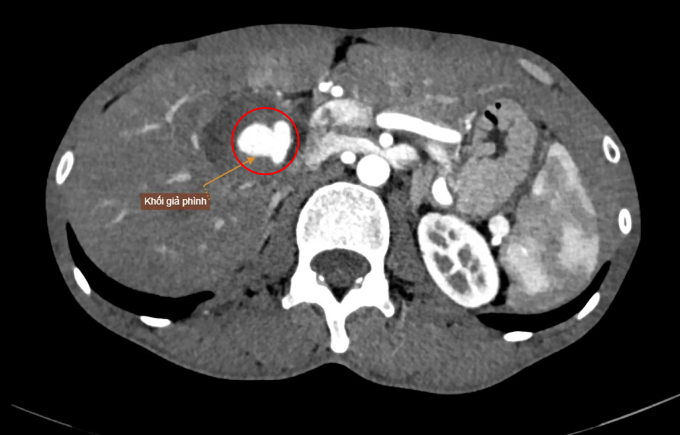

Kết quả chụp CT ổ bụng có tiêm thuốc cản quang của anh Thời tại Bệnh viện Đa khoa Tâm Anh TP HCM cho thấy nhiều túi giả phình mạch máu tại các vị trí như động mạch gan, vùng dạ dày, thận, thắt lưng. Trong đó, một khối giả phình lớn nằm tại vùng rốn gan, xuất phát từ nhánh động mạch gan phải, kích thước 40×40×65 mm chèn ép các cấu trúc lân cận, gây rối loạn tưới máu nhu mô gan và đè ép tĩnh mạch thận phải.

BS.CKI Nguyễn Trung Đức, Đơn vị Can thiệp nội mạch, cho biết người bệnh có nhiều túi giả phình rải rác, thành mạch yếu, kèm tụ máu và biến dạng giải phẫu vùng rốn gan, khiến quá trình can thiệp khó khăn. Hình ảnh kiểm tra sau thủ thuật cho thấy túi giả phình tại gan đã được tắc hoàn toàn.